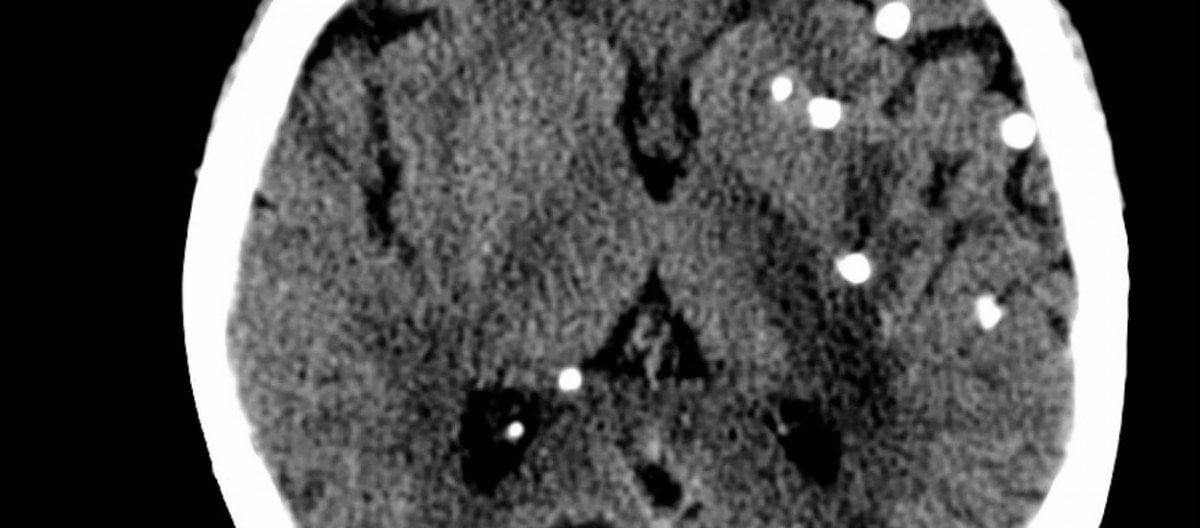

Eğer herhangi bir normal beyin MRI fotoğrafı gördüyseniz, uzman olmasanız bile, bu fotoğrafta gördüğünüzde bir anormallik olduğunu hemen anlayabilirsiniz. Evet, o beyaz noktalar bir "sorun"a işaret ederler. Ancak hayır, akla gelen ilk şey olan "kanserli doku" ya da "tümör", bu beyaz noktaların sebebi değildir. O beyaz noktalar, afiyetle beyin dokunuzdan beslenen ve burada büyüyen domuz tenyası larvalarıdır! Yani beyninizde yaşayan bir çeşit solucan...

Sistiserkoz, genel olarak domuz tenyası olarak bilinen Taenia solium türü tarafından dokuların enfekte olmasıyla karakterize edilen hastalıktır. Ancak bu tenya, özellikle beyne yerleştiğinde nörosistiserkoz denen hastalık oluşur. Bu hastalığa sahip insanlarda yıllar boyunca hiçbir semptom oluşmayabilir ve tenyalar vücut içerisinde rahatça büyüyerek güçlenebilirler. Bu süre zarfında bir domuz tenyası 1-2 santimetre boya ulaşabilir. Bu tenyalar nihayetinde yeterli boyuta ulaştığında artık dokuda şişmelere ve bozulmalara neden olurlar ve bireyde nöbetler görülmeye başlar.

Daha dehşet verici 2 bilgi verilebilir. Bunların ilki şudur: bu tenyalar vücudunuzda 1-2 tane bulunmazlar. Genelde bir defa bulaşma gerçekleştiğinde yüzlercesi ve hatta kimi zaman binlercesi vücudunuza yayılırlar. Neyse ki bunların neredeyse hepsi vücudunuzdan atılır. Ancak bazıları gereğinden fazla büyüktür (veya belli evrimsel avantajlara sahiptirler) ve vücudu konak olarak belleyerek büyümeye başlarlar. Kan akışına karışarak vücudun herhangi bir yerine ulaşabilirler ve burada büyürler. İkinci dehşet verici bilgi ise, umulanın ve sanılanın aksine bu tenyaların hiç de seyrek olmayışıdır. Tam tersine, modern dünyada sinir nöbetlerinin 1 numaralı sorumlusu bu solucanlardır.